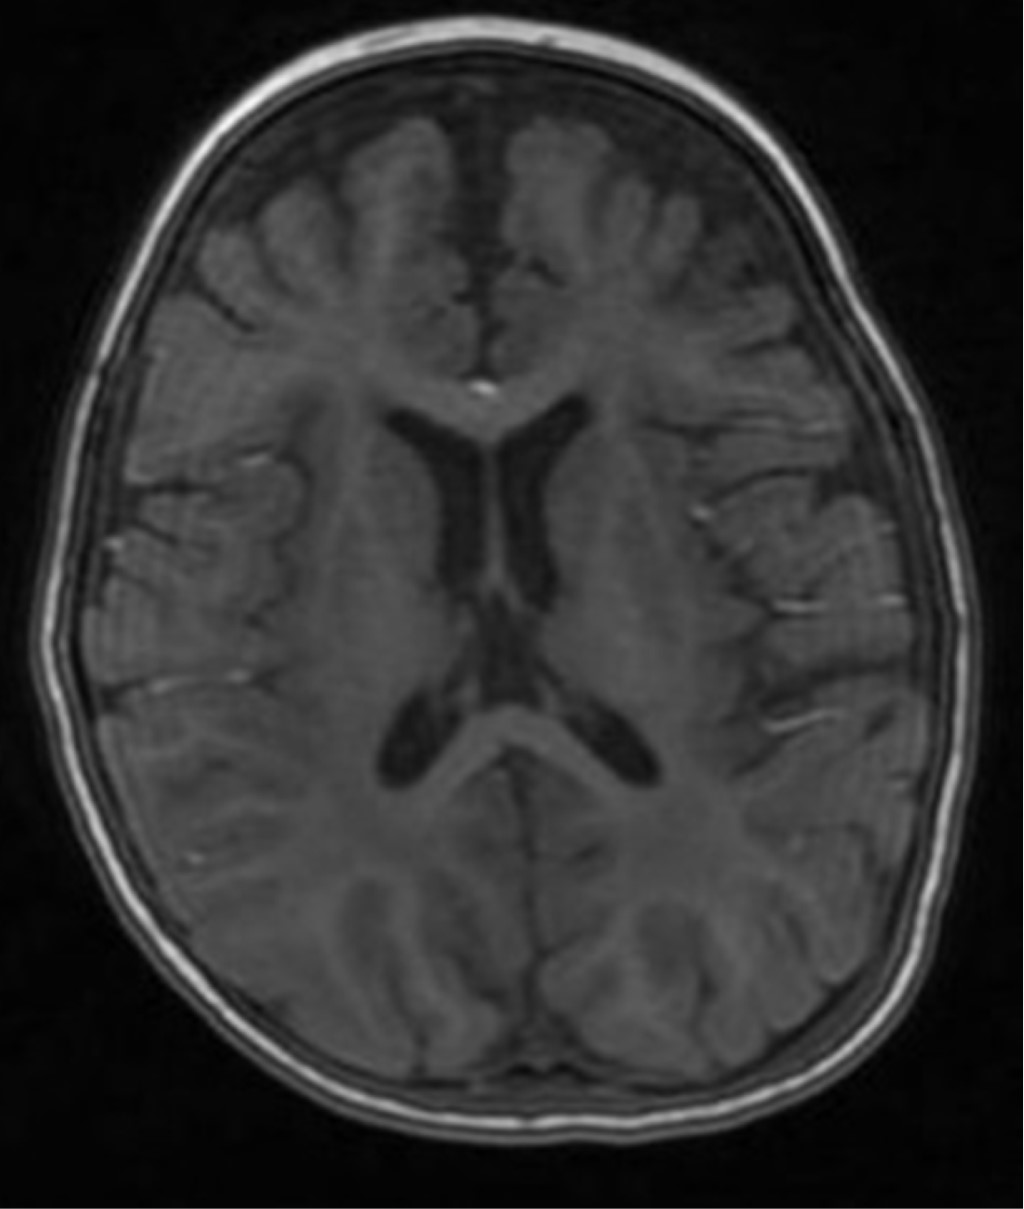

Figure 2